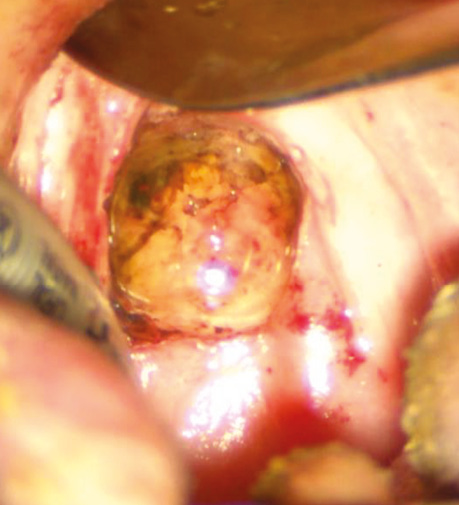

Пацієнт В., 40 років. Встановлено діагноз — плоскоклітинна карцинома м’якого піднебіння T2N0M0. Проведено трансоральну CO₂-лазерну резекцію м’якого піднебіння. Етапи хірургічного втручання представлені на рис. 1–2.

Рис. 1. Трансоральна CO₂-лазерна резекція м’якого піднебіння із попередньою візуалізацією зони ураження за допомогою індоціанінового зеленого барвника (ICG) для точнішого визначення меж пухлинного ураження